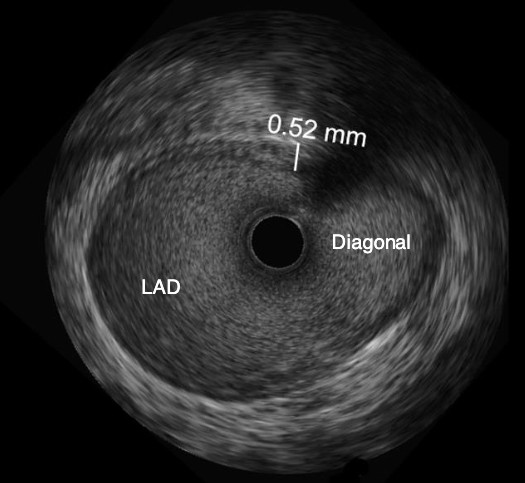

Catéter para toma de imágenes coronarias Opticross de 40 MHz vs. Catéter para toma de imágenes coronarias Opticross de 60 MHz

El Catéter para toma de imágenes coronarias Opticross de 60 MHz proporciona una mayor visibilidad del stent con una resolución más clara para confirmar la aposición adecuada del stent a la pared del vaso.

OPTICROSS 40 MHz

OPTICROSS HD Imaging Catheter 40MHz

Axial resolution: 38 µm

OPTICROSS 60 MHz

Catéter de imágenes OPTICROSS HD 60MHz

Resolución axial: 22 µm